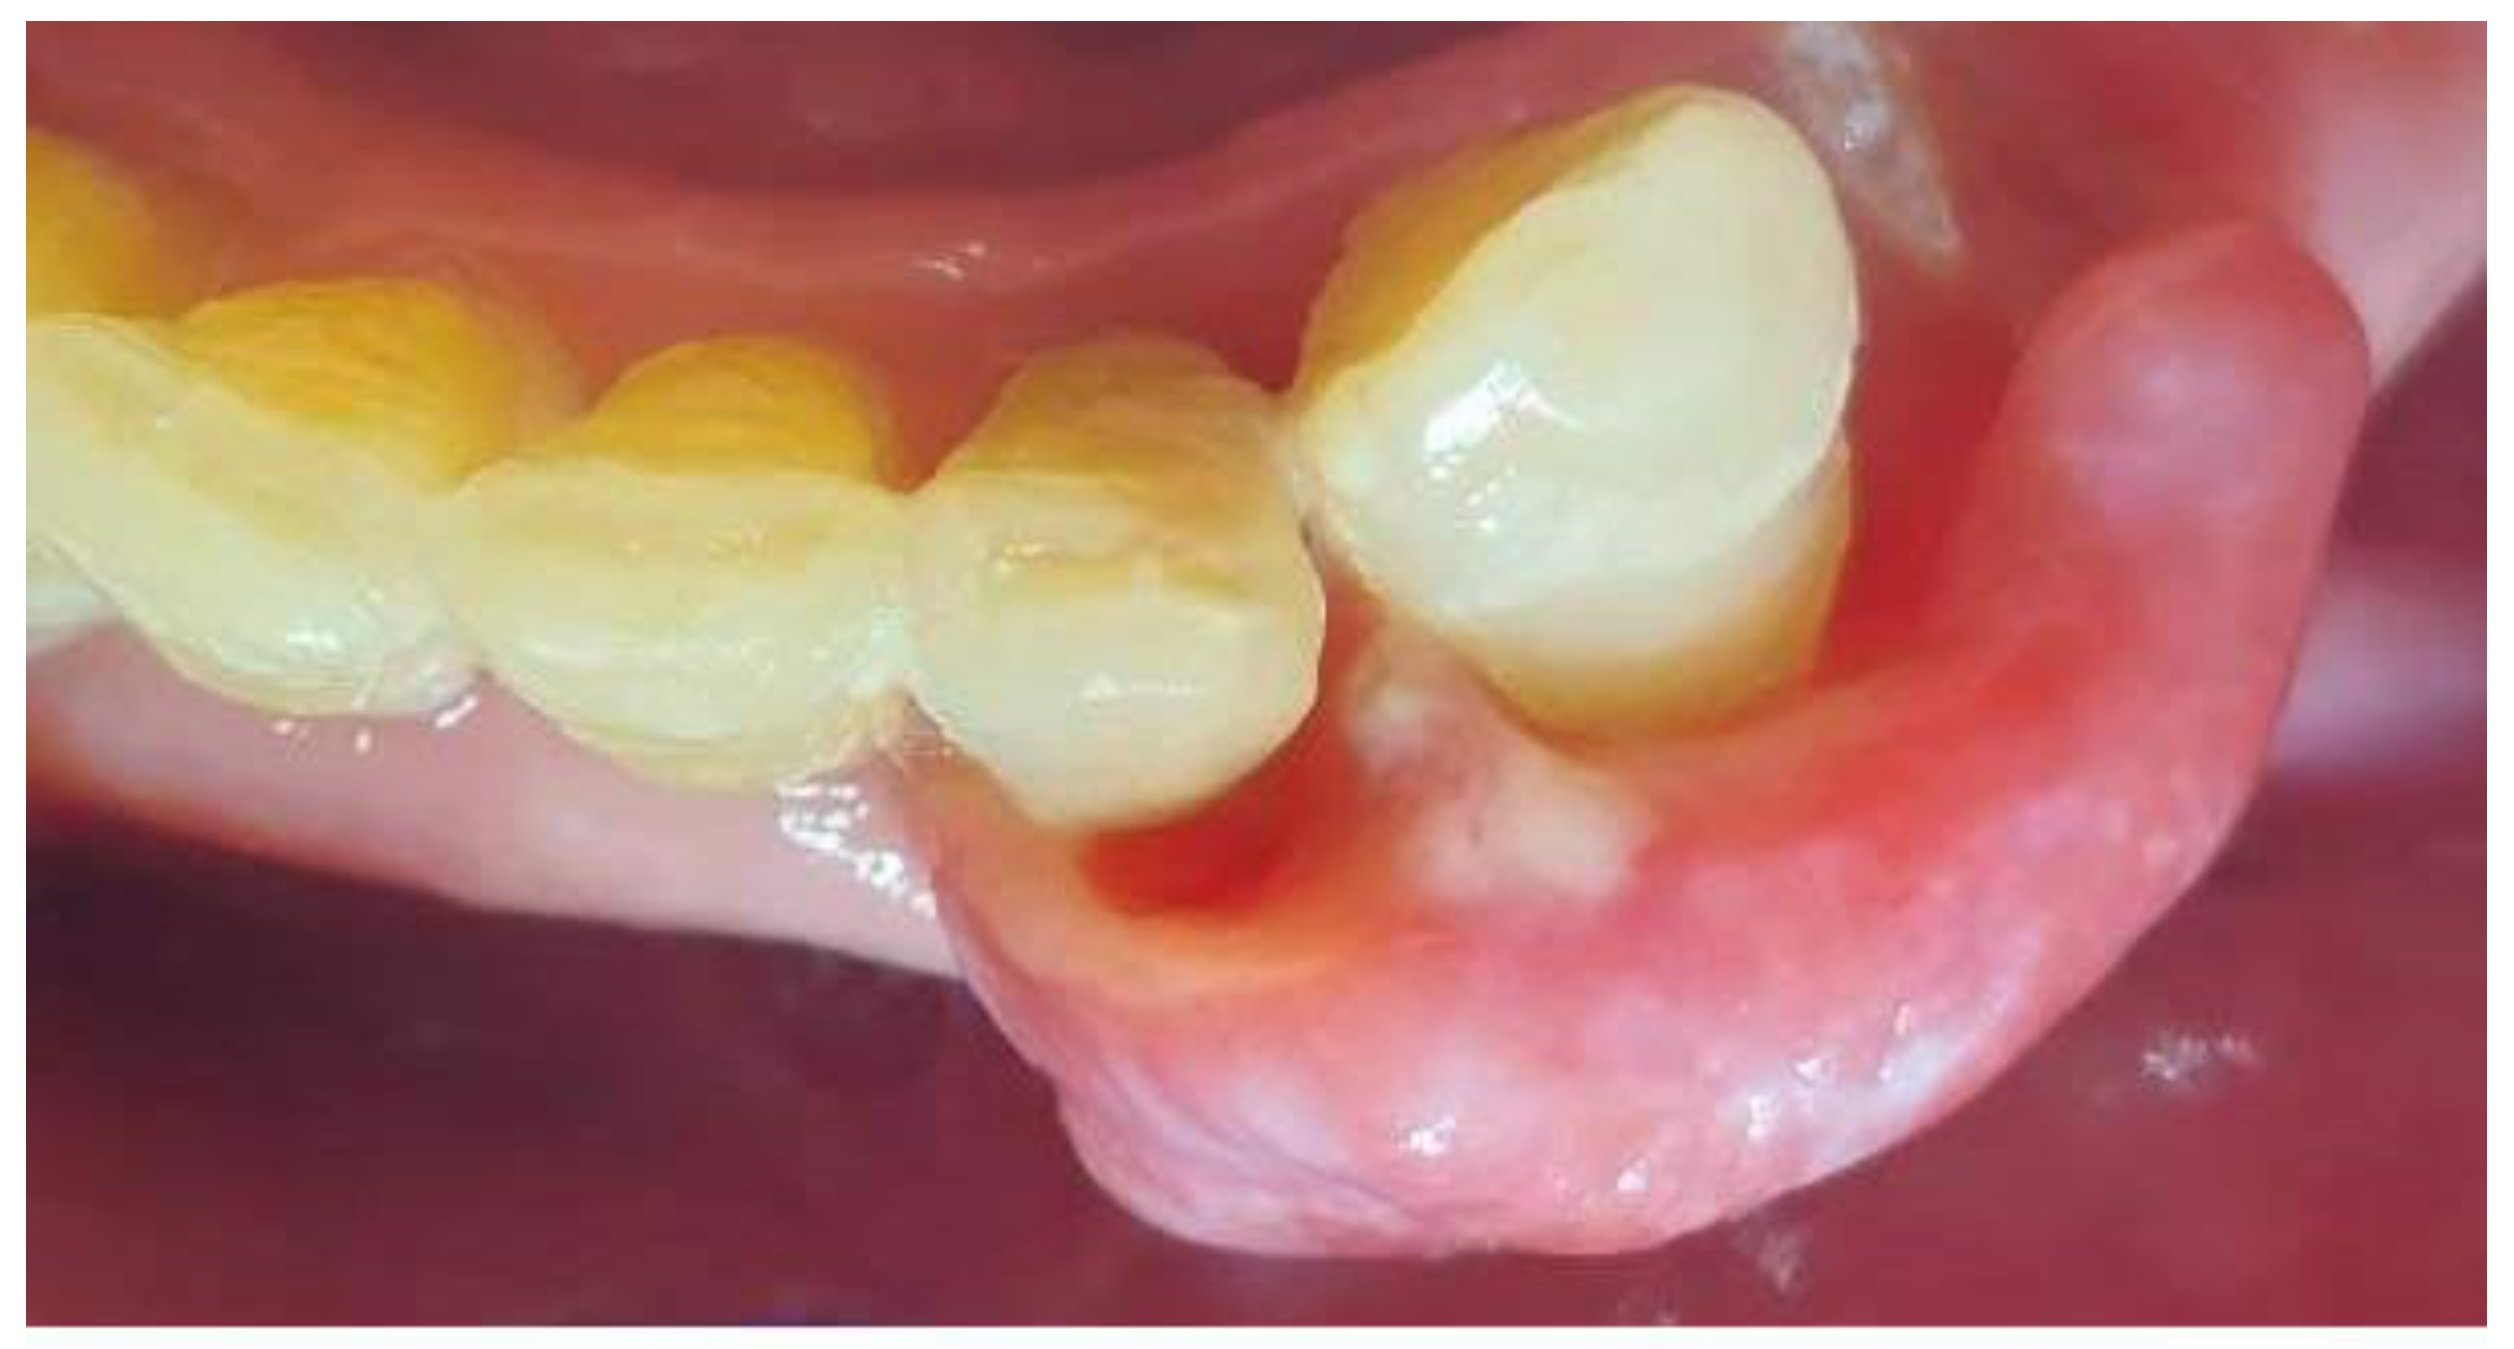

2. Case Presentation